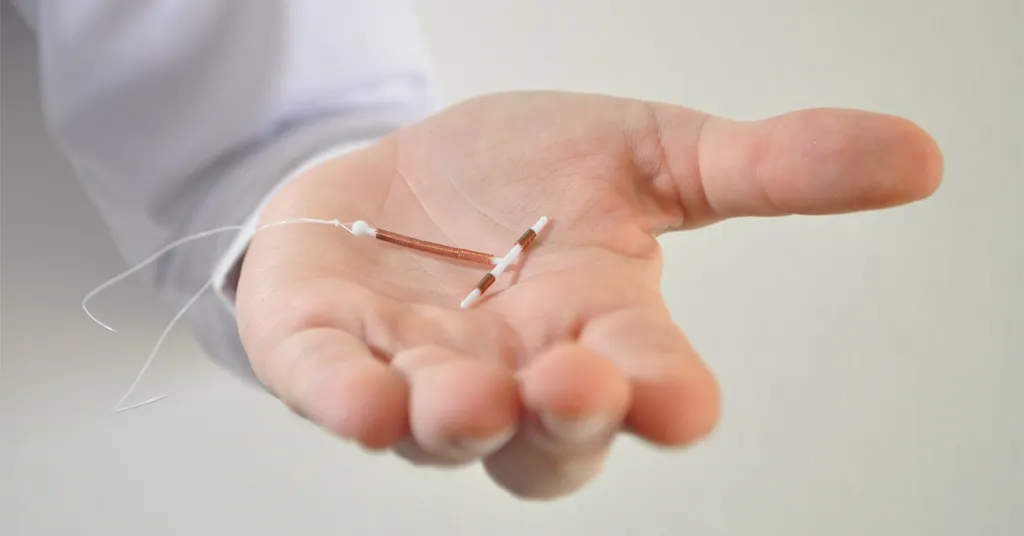

Long-Acting Reversible Contraception: IUDs and Implants